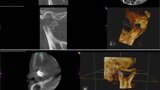

Ryc. 4_ Zdjęcie pantomograficzne przed urazem (po lewo) i po urazie (po prawo).